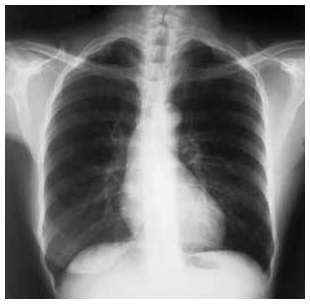

Caso clínico para os itens de 50 a 60

Uma mulher com 68 anos de idade foi atendida no ambulatório de um posto de saúde, com relato de tosse produtiva com

expectoração mucoide, que vem ocorrendo há mais de três anos. Informou ser tabagista (45 maços/ano) e que, nos últimos seis meses,

passou a ter dispneia progressiva aos esforços físicos. O exame físico mostrou: paciente dispneica leve, acianótica, pressão arterial de

120 mmHg × 80 mmHg, frequência cardíaca de 80 bpm, frequência respiratória de 22 irpm, com ritmo cardíaco regular em 2 tempos,

bulhas cardíacas hipofonéticas e ausência de sopros à ausculta cardíaca, diâmetro anteroposterior da caixa torácica aumentado, presença

de hipersonoridade à percussão do tórax e murmúrio vesicular reduzido de forma difusa, com roncos esparsos à ausculta pulmonar; o

restante do exame não apresentou anormalidades. Abaixo é reproduzida a radiografia do tórax em projeção posteroanterior realizada para

essa paciente.

Tendo por base as informações clínicas e a radiografia de tórax apresentadas, julgue os itens a seguir.